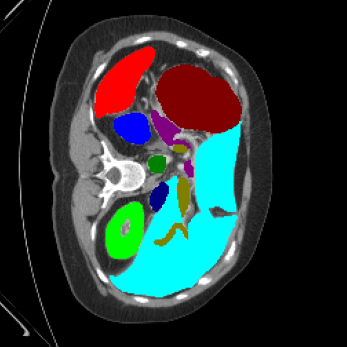

| Ground Truth | LoGoNet | DiNTS Search |

|---|---|---|

![]() |

We begin by qualitatively inspecting our model. Figure 3 compares the output of LoGoNet to the best performing baseline model in BTCV dataset, i.e., DiNTS Search (more qualitative comparisons can be found in appendix section 11). We see that our model particularly excels in segmenting organ boundaries. This can be attributed to our effective strategy for extracting local-range dependencies, which plays a crucial role in extracting details from input data. Our model’s adeptness in capturing long-range dependencies allows it to grasp contextual information that extends over significant distances within the data. Simultaneously, its proficiency in handling short-range dependencies ensures precision in capturing localized patterns.